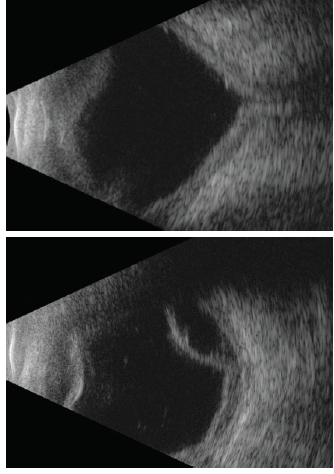

Over the next 15 months, multiple injections were required as the retinal detachment waxed and waned but never completely resolved. Then, approximately 6 weeks after the last intravitreal injection, the child developed redness of the eye, lid swelling, and decreased oral intake. EUA revealed intact conjunctiva and hypopyon in the anterior chamber. The patient was diagnosed with severe endophthalmitis (Figure 4). Vitreous biopsy was performed and intravitreal antibiotic injections were given, and the culture was negative. Over the following 2 months, the retina became totally detached, and the eye was chronically inflamed and painful. The eye was enucleated shortly thereafter.

Figure 4. Color anterior segment photograph and echographic images demonstrate turbid aqueous and hypopyon in the anterior chamber. The vitreous was filled with debris with extensive membrane formation.